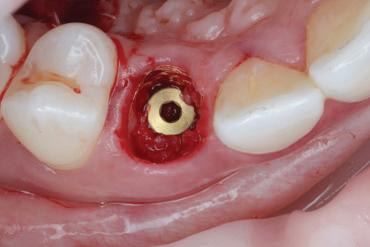

Another key reason for a referral is that a dental professional does not have the adequate training to provide predictable, safe care. This is often the case in more advanced treatments, such as endodontic therapy or long-term orthodontic care, as well as surgical needs such as dental implant placement or tissue augmentation.